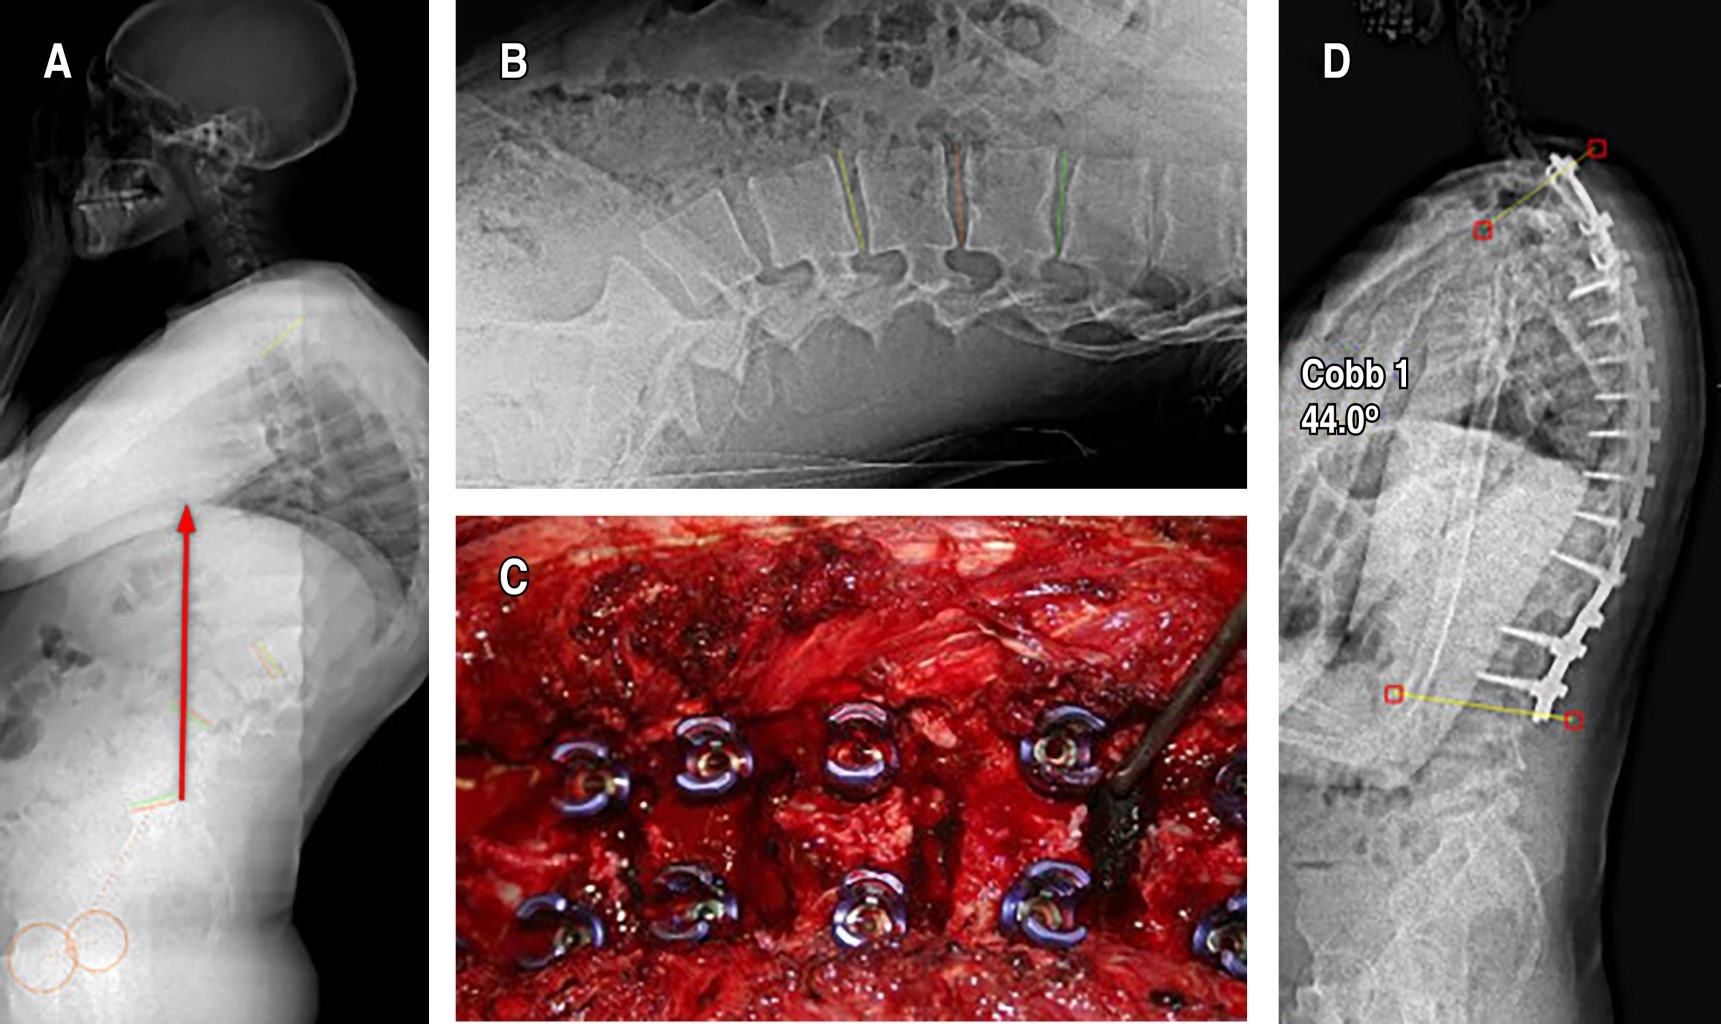

Exploración física. Comprende la valoración global del tipo de perfil (normal, aumento de las curvaturas raquídeas sagitales, inversión de las curvaturas con cifosis dorsolumbar o lumbar) y el examen del equilibrio frontal y sagital de la columna y de la pelvis con regla milimétrica y plomada. El examen del perfil consiste en la medición de las flechas sagitales y la determinación de la parte alta de la cifosis (Figura 1).6

Debe realizarse una radiografía de columna en proyección lateral con el paciente de pie y con los hombros y brazos en 90°, o sobre la clavícula ipsilateral (en posición clavicular). Para la medición del ángulo de cifosis, se seleccionan las vértebras finales craneal y caudal incluidas en la deformidad. La medida del grado de acuñamiento se obtiene del ángulo de intersección de las tangentes sobre los platillos superior e inferior de cada cuerpo vertebral.9 El criterio diagnóstico establece un acuñamiento superior a los 5° en al menos tres vertebras consecutivas en el ápex de la cifosis (Figura 2).1 También son hallazgos comunes en la radiología la presencia de nódulos de Schmorl, la irregularidad y el adelgazamiento de los platillos vertebrales y el pinzamiento del espacio discal. Para la medición del grado de flexibilidad de la hipercifosis se emplea la proyección lateral con el paciente en hiperextensión sobre una cuña o pivote (Figura 3).1 En la enfermedad clásica tipo I, el ápex de la cifosis se localiza entre T6 y T9. En el tipo II, el ápex de la cifosis se localiza sobre la charnela toracolumbar.10

Estos pacientes suelen presentar un equilibrio sagital global negativo, que se demuestra mediante el dibujo de la plomada desde el centro del cuerpo de C7 hasta el platillo sacro en la radiografía lateral de columna. Se define el equilibrio sagital negativo cuando la plomada cae por detrás de la esquina posterosuperior del platillo sacro.11

La fusión anteroposterior en dos etapas también se asoció con menor incidencia de falla de la unión cuando se usaron varias formas de instrumentación, incluida la instrumentación de Cotrel-Dubousset y las varillas de Luque. Esto llevó a la recomendación del abordaje en dos etapas como el estándar de oro en el tratamiento quirúrgico de la ES. Sin embargo, con el avance de las técnicas quirúrgicas (osteotomías de Ponte) y la instrumentación (tornillos pediculares posteriores multisegmentarios), existe un cambio hacia un abordaje solo posterior (Figura 5).16,18

En los años 80 y 90, la recomendación para la corrección de la curvatura severa era el abordaje dual.19 Desde que Bradford y colaboradores20 realizaron el primer informe sobre la fusión posterior en el tratamiento de la ES, las indicaciones quirúrgicas, así como las técnicas operativas, han cambiado significativamente, y la fusión posterior de una sola etapa moderna ahora incorpora típicamente una osteotomía de Smith-Petersen o Ponte.